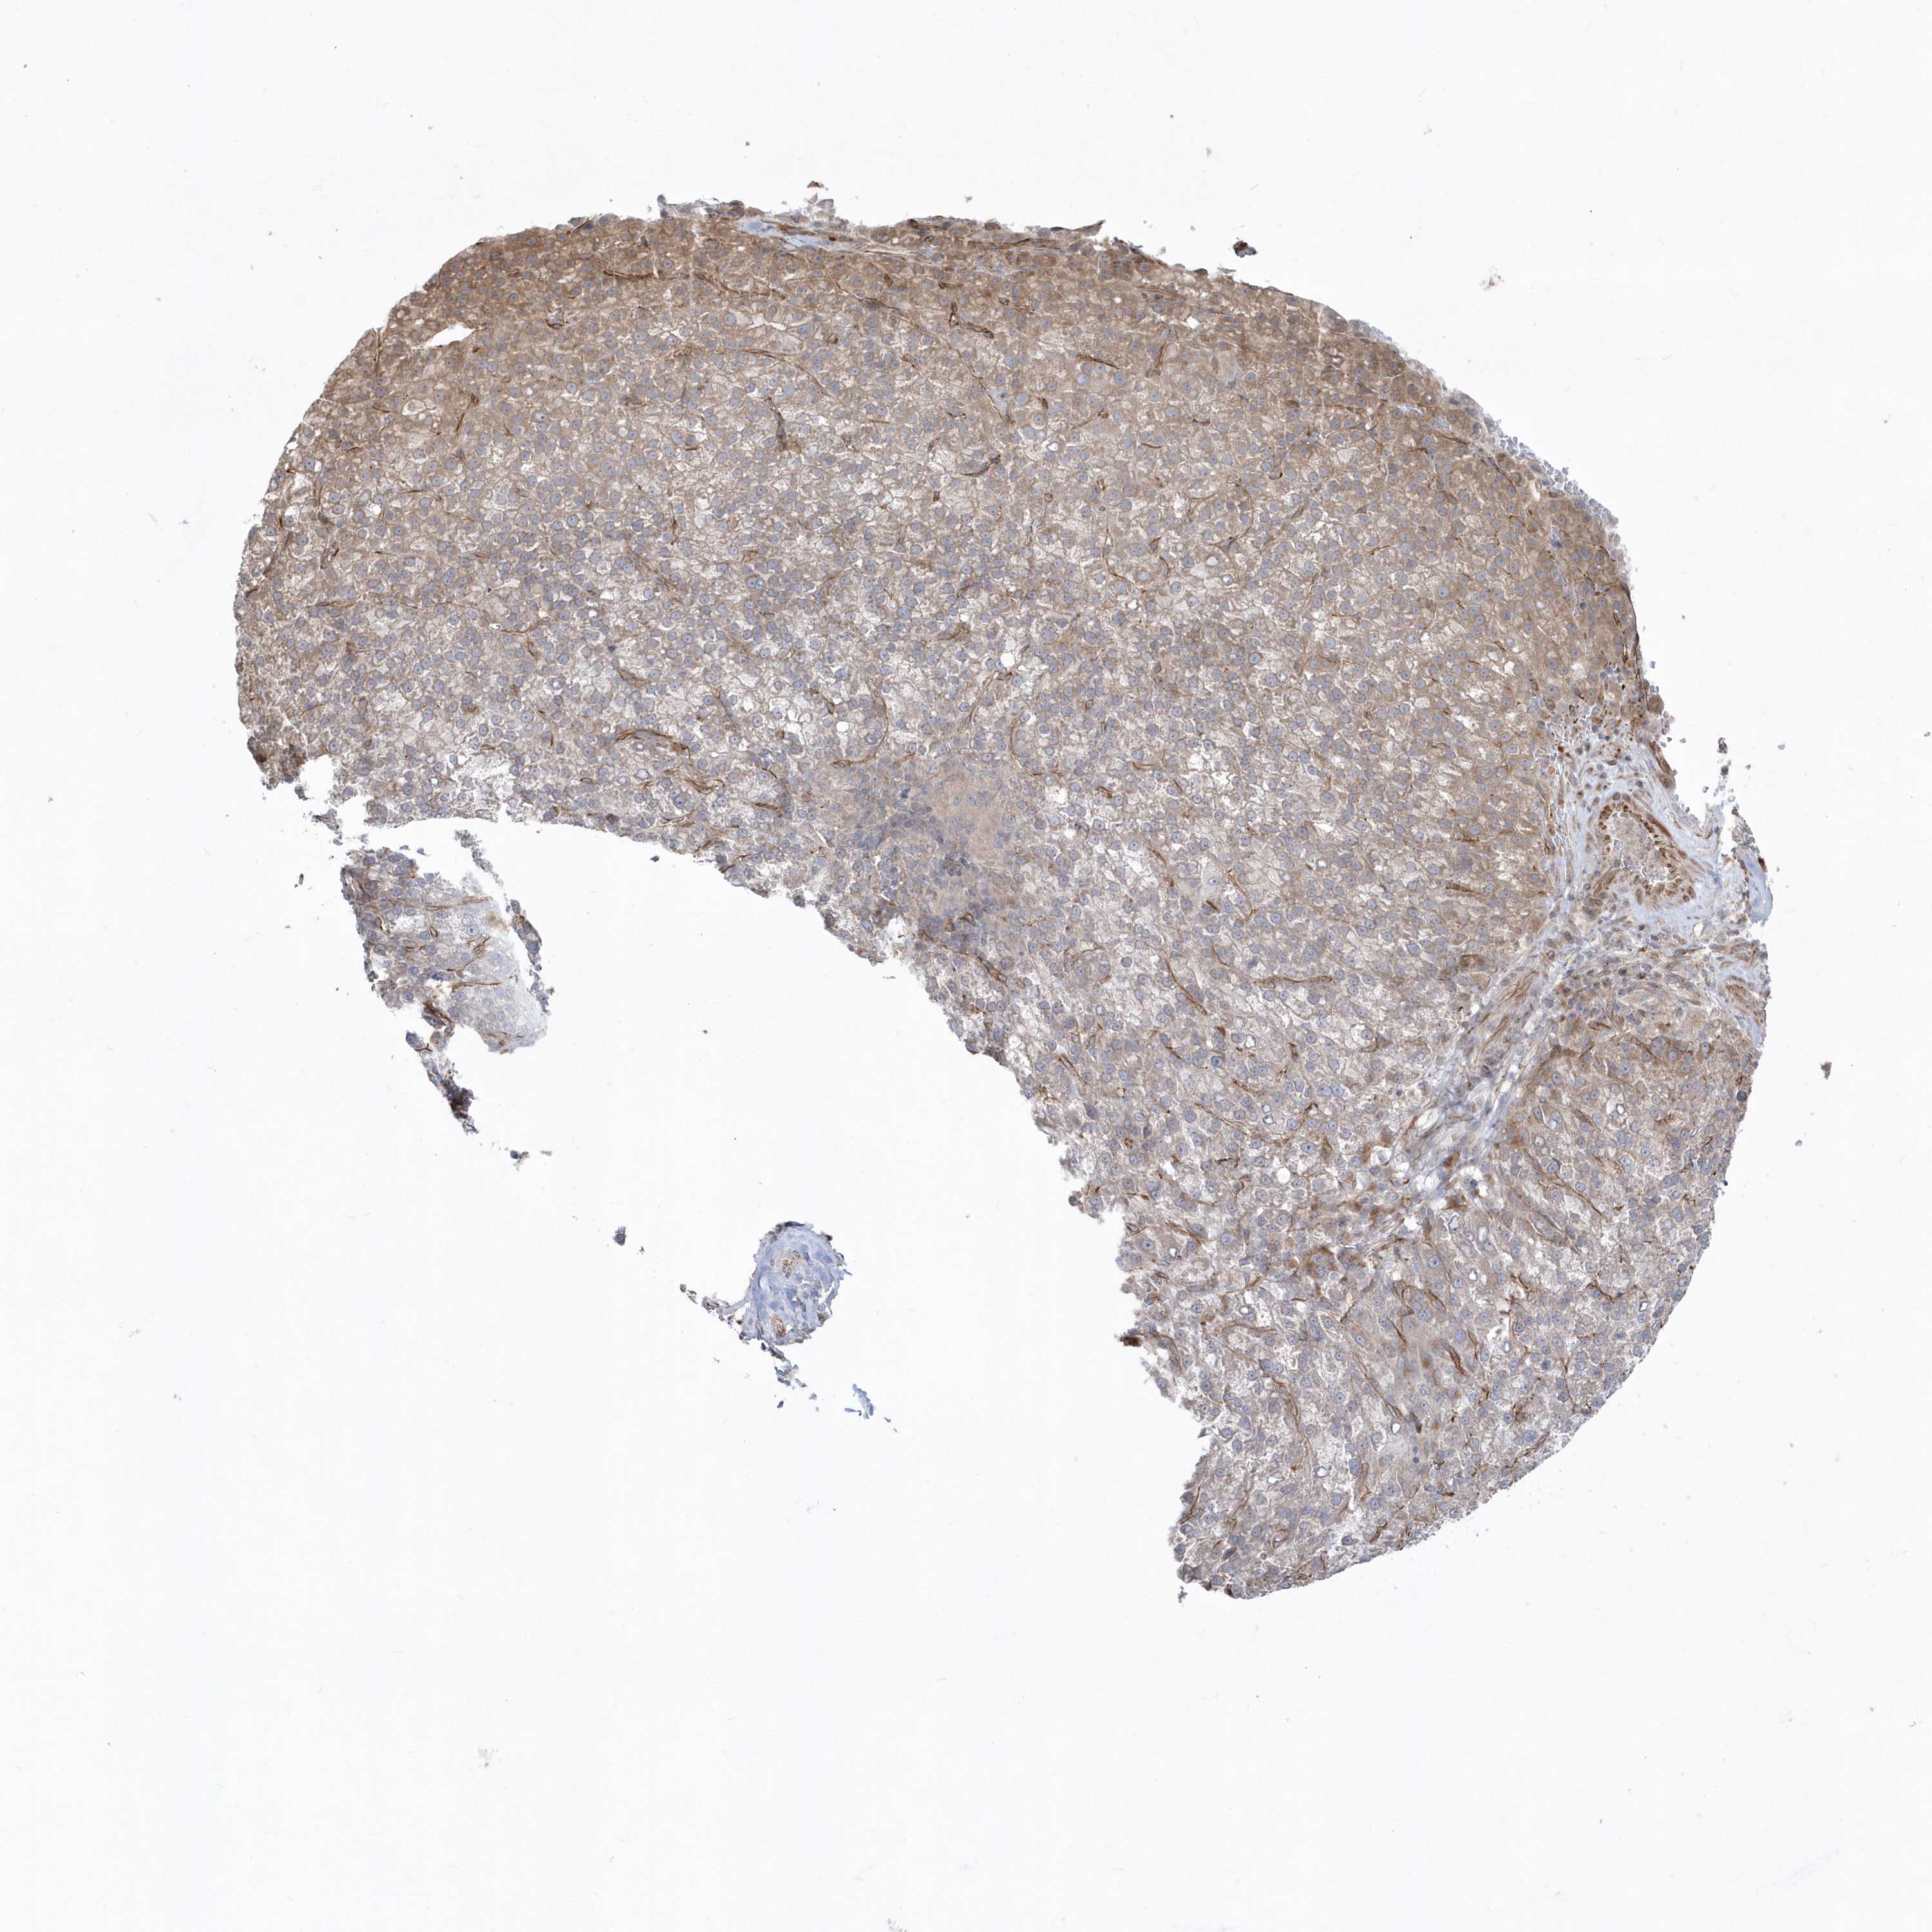

LIVER CANCER - Protein expressioni

A mouse-over function shows sample information and annotation data. Click on an image to view it in a full screen mode. Samples can be filtered based on level of antibody staining by selecting one or several of the following categories: high, medium, low and not detected. The assay and annotation is described here.

Note that samples used for immunohistochemistry by the Human Protein Atlas do not correspond to samples in the TCGA dataset.

Antibody stainingi

Antibody staining in the annotated cell types in the current human tissue is reported as not detected, low, medium, or high, based on conventional immunohistochemistry profiling in selected tissues. This score is based on the combination of the staining intensity and fraction of stained cells.

Each image is clickable and will lead to virtual microscopy that enables deeper exploration of all samples and also displays staining intensity scores, fraction scores and subcellular localization as well as patient and tissue information for each sample.

Antibody HPA036160

Staining

High

Medium

Low

Not detected

Intensity

Strong

Moderate

Weak

Negative

Quantity

>75%

75%-25%

<25%

None

Location

Nuclear

Cytoplasmic/membranous

Cytoplasmic/membranous,nuclear

Cholangiocarcinoma

Carcinoma, Hepatocellular, NOS